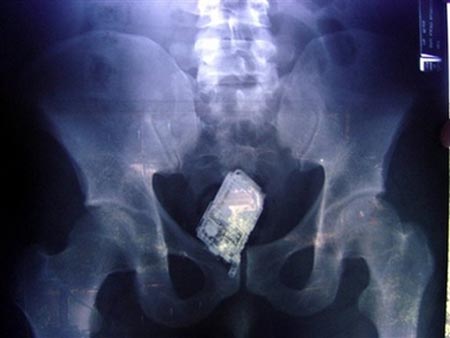

File:Butt camera phone.jpg

Butt_camera_phone.jpg (450 × 338 pixels, file size: 17 KB, MIME type: image/jpeg)